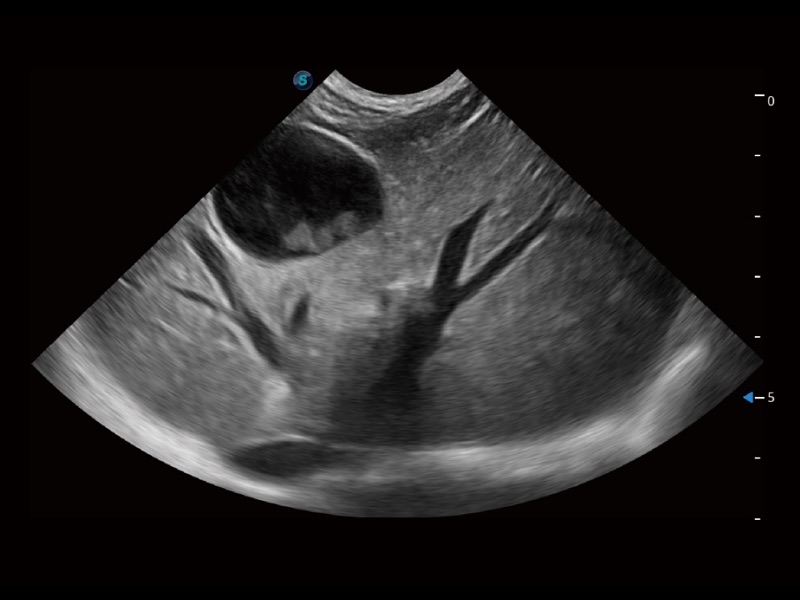

動(dòng)物是人類最親密的朋友和最值得信賴的伙伴。開立醫(yī)療也一直致力于探索動(dòng)物專用的超聲影像解決方案。全新推出的ProPet系列,是開立在動(dòng)物超聲影像智能化、專業(yè)化、精準(zhǔn)化的一次跨越式革新。動(dòng)物不能用言語來表述自己的不適,通過超聲影像,ProPet系列搭建了動(dòng)物醫(yī)生與不同物種溝通的“橋梁”,為動(dòng)物醫(yī)生注入了“治愈之力”。 ProPet 70將是您值得信賴的超聲伙伴。它配備了復(fù)合材料線陣探頭,幫助動(dòng)物醫(yī)生獲得卓越精準(zhǔn)的臨床圖像。同時(shí)ProPet 70直觀便捷的操作體驗(yàn)以及專業(yè)的測(cè)量工具,可為不同體型和生理結(jié)構(gòu)的動(dòng)物帶來全面臨床評(píng)估,切實(shí)為動(dòng)物醫(yī)生提供智能、專業(yè)、精準(zhǔn)的超聲影像解決方案。

ProPet 70 進(jìn)一步提升了微米成像算法,更加注重對(duì)基礎(chǔ)原始圖像的還原和保留,在有效減少斑點(diǎn)噪聲、增強(qiáng)組織邊界顯示的同時(shí),避免過度優(yōu)化丟失真實(shí)的解剖信息。

ProPet 70專為動(dòng)物醫(yī)生設(shè)計(jì),對(duì)不同的動(dòng)物體型和生理結(jié)構(gòu)作出了針對(duì)性的優(yōu)化。通過動(dòng)物影像專用軟件,可滿足個(gè)性化的應(yīng)用需求,幫助動(dòng)物醫(yī)生獲得更精確的診斷數(shù)據(jù)。

ProPet 70 全新的動(dòng)物超聲智能軟件和豐富的探頭群,為動(dòng)物醫(yī)生提供了高清晰度和精細(xì)分辨率的圖像,無論在寵物、馬科、畜牧還是實(shí)驗(yàn)室動(dòng)物等應(yīng)用中都可以輕松應(yīng)對(duì),為您的日常工作帶來滿意的體驗(yàn)。